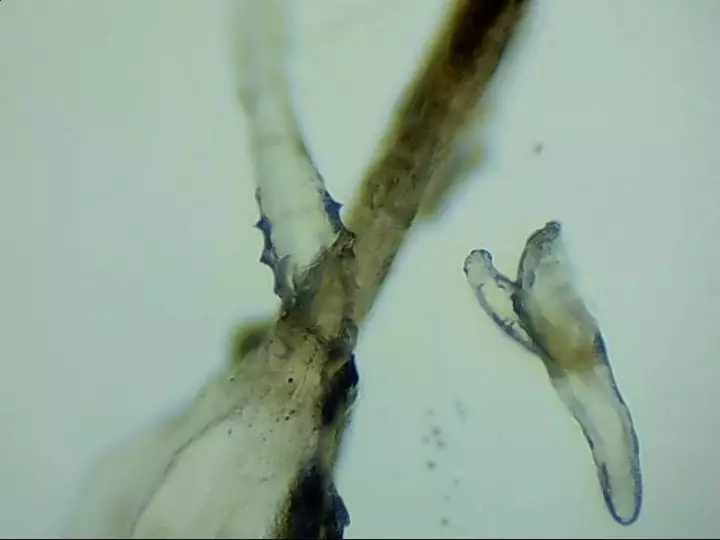

蠕形螨性瞼緣炎是蠕形螨感染瞼緣所致,在臨床上比較常見,患病后瞼緣皮膚、睫毛毛囊及其腺體、瞼板腺會引起炎癥,并可出現(xiàn)眼癢、異物感、眼干、瞼緣充血、鱗屑、睫毛根部袖套狀分泌物及睫毛脫落等臨床表現(xiàn),嚴重者可并發(fā)結(jié)膜及角膜病變。

蠕形螨是常見的人體外寄生蟲,也是瞼緣炎患者眼上最常見的寄生蟲。據(jù)報道,瞼緣炎患者中蠕形螨的檢出率達23.8%~90%。

寄生在人體的蠕形螨以毛囊蠕形螨為主,皮脂蠕形螨次之。在眼部,毛囊蠕形螨寄生于睫毛毛囊,而皮脂蠕形螨則分布于睫毛毛囊的皮脂腺和瞼板腺內(nèi)。兩種螨蟲經(jīng)常生活在睫毛和眉毛根部,它們通過生產(chǎn)的卵、排泄的廢物和分泌的分泌物導(dǎo)致過敏反應(yīng),并在人體免疫系統(tǒng)變?nèi)鯐r引起眼部感染。

蠕形螨性瞼緣炎門診配備有光學(xué)顯微鏡鏡檢、活體激光共聚焦顯微鏡檢查等高新設(shè)備可作出精準診斷。并有多種治療手段全方面驅(qū)逐、殺死螨蟲。